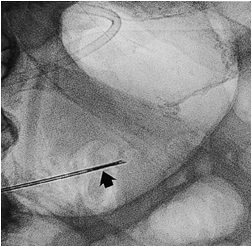

穿刺进针:侧位、斜位透视进针 ![]() 后前位进针不能确定进针的深度。侧、斜位进针可以确定进针的深度, 进针速度快。进针过程中用注射器保持负压。一旦充水的注射器出现气泡,提示针尖已经进入胃腔。 一、 推:Sacks-Vine 技术:一种直接经皮胃造瘘技术。胃腔穿刺成功后Seldinger法置换胃造瘘管进入胃腔内,技术成功率高。